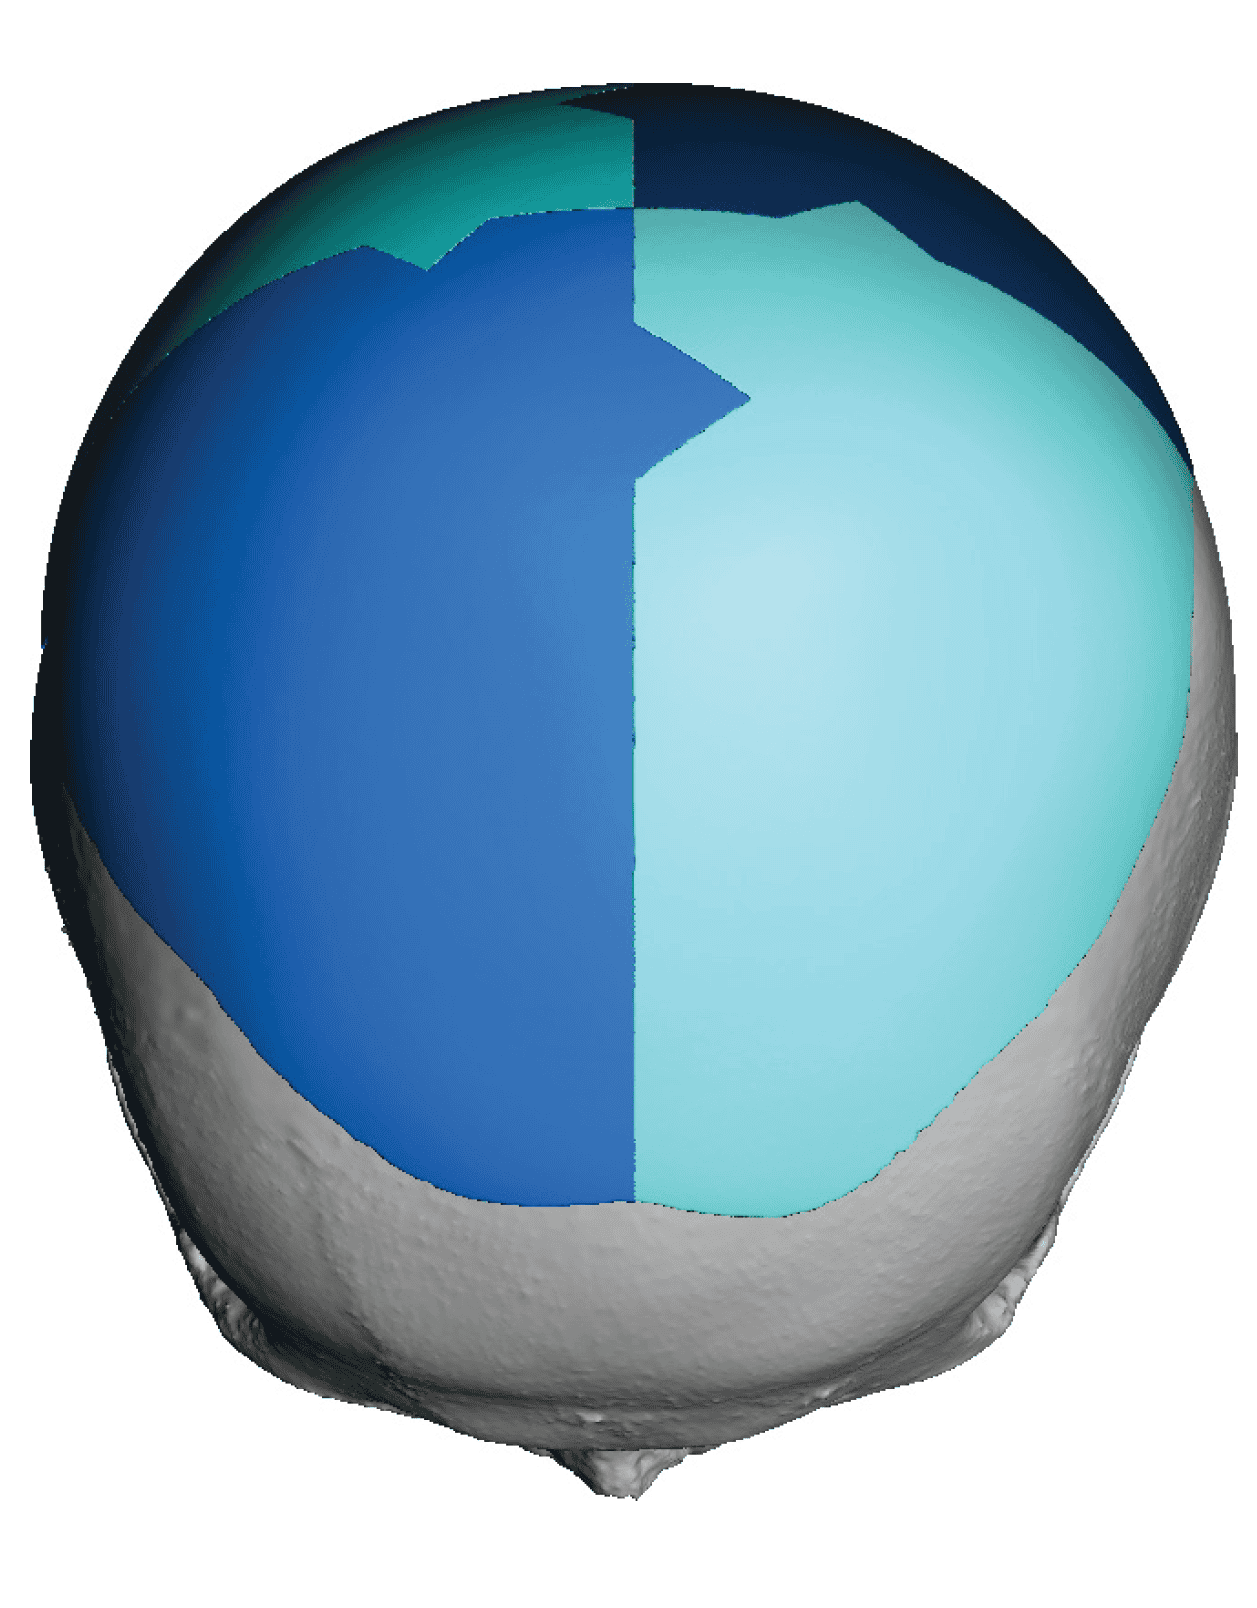

Patient 110

Desire for head shape asymmetry improvement as the final stage of total skull reshaping surgeries. (previous skull implants are in green color)

Placement of custom temporal implant through an incision behind the ear.

Desire for head shape asymmetry improvement as the final stage of total skull reshaping surgeries. (previous skull implants are in green color)

Placement of custom temporal implant through an incision behind the ear.